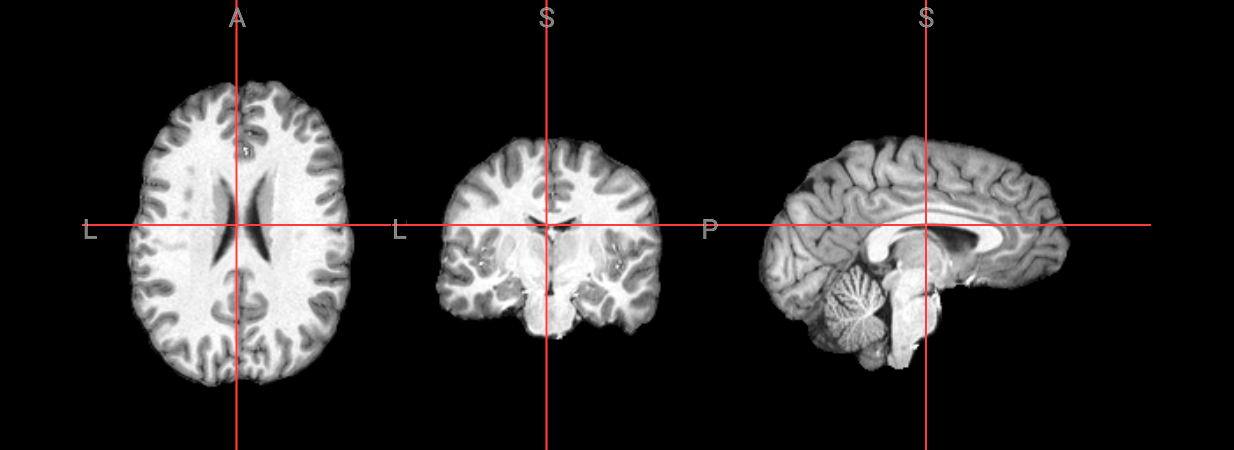

Since fMRI studies focus on brain tissue, our first step is to remove the skull and non-brain areas from the image.

In order to analyze fMRI data, you will need to load an fMRI analysis package. In this example we will use the following packages and algorithms to skull-strip the anatomical image:

Advanced Normalization Tools (ANTs): antsBrainExtraction.sh

Analysis of Functional NeuroImages (AFNI): 3dSkullStrip

FreeSurfer: SynthStrip

FSL (FMRIB Software Library, created by the University of Oxford): BET - Brain Extraction Tool